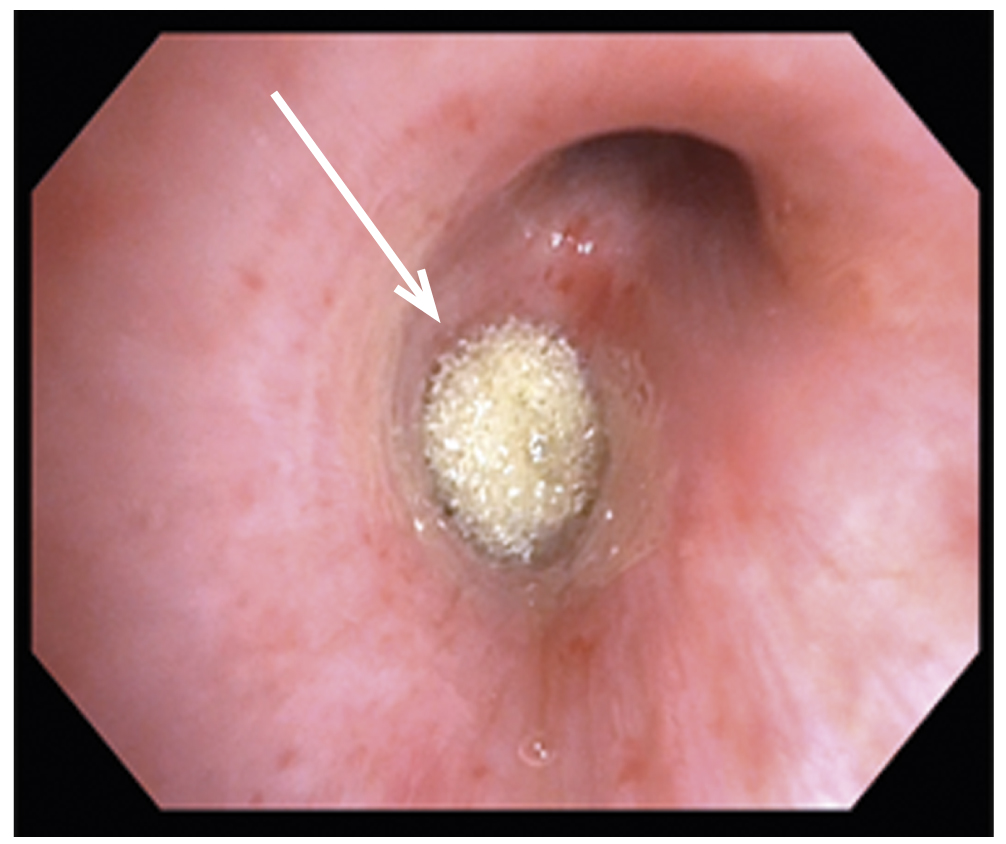

Повторное исследование для удаления бронхоблокатора выполняли через 7 сут в условиях операционной с рентгенологическим контролем (С-дуга). При ЛТБС через воздуховод I-GEL с помощью эндоскопических щипцов типа «крысиный зуб» из промежуточного бронха без технических сложностей произведено удаление 3-х полиуретановых блокаторов. При контрольном осмотре визуализирован поверхностный дефект слизистой промежуточного бронха длиной 5–6 мм с признаками выраженной эпителизации (рис. 5).

Рис. 5. Эндоскопическая картина после удаления бронхоблокаторов: эпителизация травматического разрыва промежуточного бронха (стрелка).

Fig. 5. Endoscopic picture after removal of bronchoblockers: epithelialization of traumatic rupture of the intermediate bronchus (arrow).

В просвете всех видимых бронхов средней и нижней долей справа имелось умеренное количество вязкого слизисто-гнойного содержимого. Выполнена санация просвета трахеи и бронхов с промыванием антисептическим раствором в объёме до 15 мл. После удаления бронхоблокаторов сброс воздуха по дренажу из плевральной полости отсутствовал, при рентгенологическом контроле отмечено расправление средней и нижней долей правого лёгкого, дренаж из плевральной полости был удалён. На протяжении всего исследования вентиляционных нарушений отмечено не было. При контрольной СКТ после удаления бронхоблокаторов отмечено восстановление пневматизации и объёма правого лёгкого при сохранении застойно-воспалительных изменений в нижней доле правого лёгкого (рис. 6).